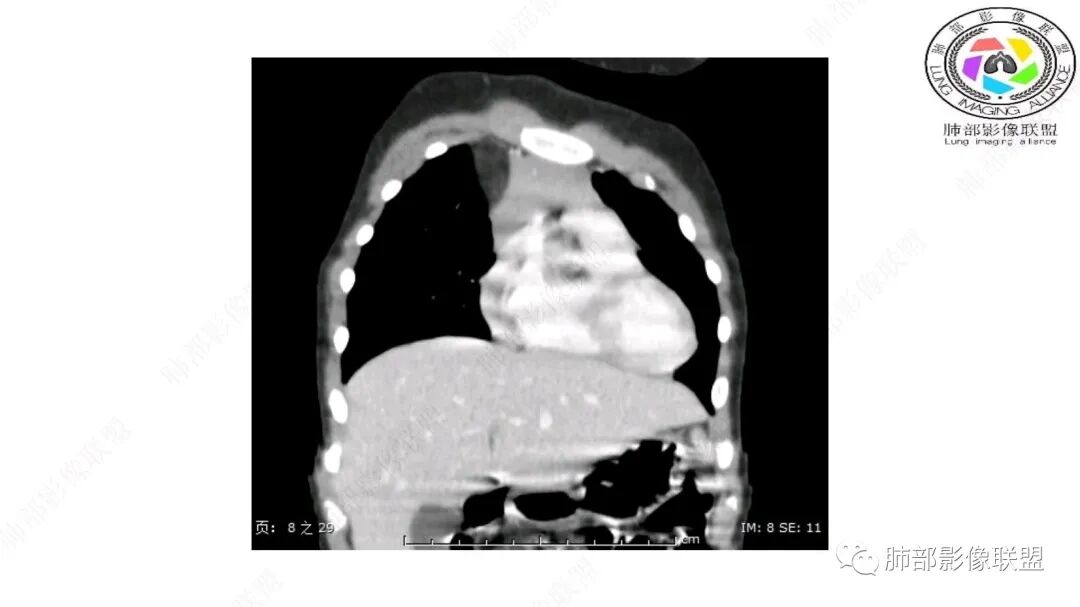

第一个问题:定位:肺内?纵隔?

病灶属于交界区,主体位于肺内,占位效应明显,前方突入胸壁,胸腺受压变形,胸膜显示欠清楚;病灶包绕上叶肺动脉;似乎有体动脉供血。符合肺内的点:包绕上叶肺动脉分支;符合纵隔的点:前方似乎突入胸壁,与胸腺关系比较密切,但是与上腔静脉的关系提示病灶不支持纵隔来源,前纵隔的常规会将上腔静脉受压后移、外移,这是不符合的。

从这个角度符合肺内的,有一点不太踏实的是:似乎突入前胸壁。

手术记录:见右肺上叶肿物,肿物与右肺上叶关系密切。与纵隔无粘连,逐步分离肿物,见肿物大小约6cm*5cm,边界清楚,于右肺上叶粘连,边界清楚,肿物包绕右肺上叶血管及支气管。超声刀逐步游离肿物,完整切除肿物,右肺上叶肺组织无破溃,表面无出血。

1.右上肺-纵隔交界区巨块影,主体位于右肺一侧,紧贴胸腺、头臂干、右锁骨下动脉、上腔静脉、奇静脉等,不能分离,但病灶整体边界清楚。注意上述相邻腔静脉等结构未见受压变形,纵隔亦未见明显向左推移,至少提示两点:

2.肺动脉穿行也许是肺内来源最重要支持点!